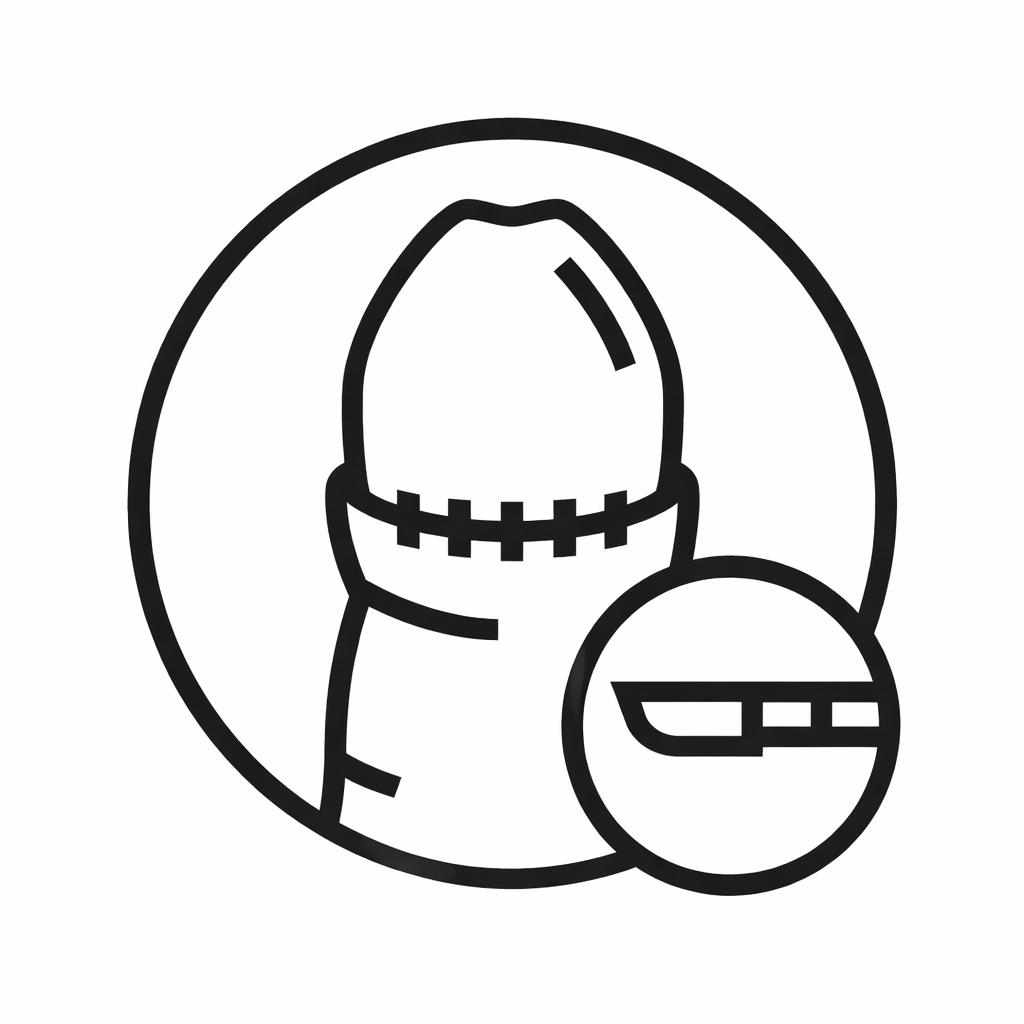

Phimosis Surgery (Circumcision)

Circumcision surgery treating phimosis and improving hygiene and comfort.